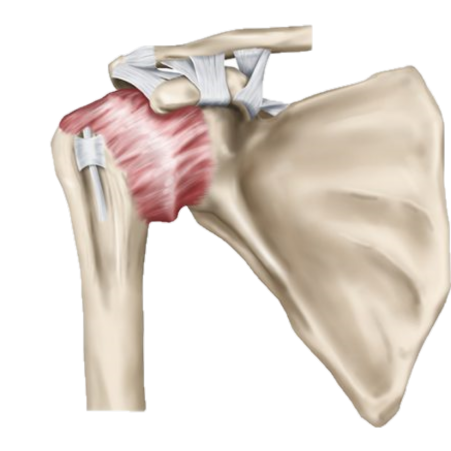

Frozen shoulder, also known as adhesive capsulitis, is a condition where the shoulder becomes stiff, painful, and difficult to move. It happens when the connective tissue around the shoulder joint becomes thickened and tight, limiting motion and causing discomfort.